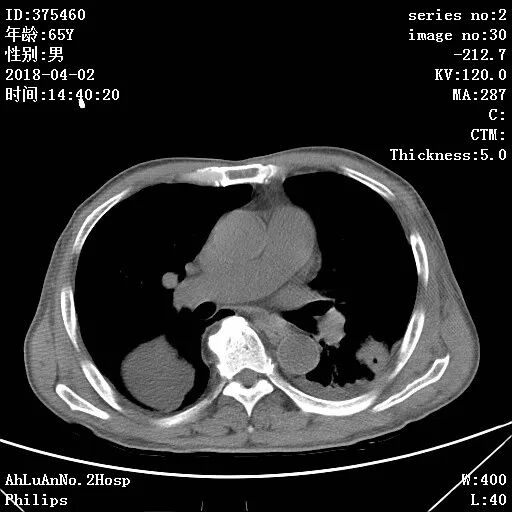

患者男,65岁,因“咳嗽、咳痰1月余,发热1周”入院。

两肺可见多发斑片状及气囊样阴影,部分气囊样影内可见气液平面,两侧胸膜腔可见少量液性密度影聚集。

结果:金黄色葡萄球菌肺炎

显示,白细胞计数和中性粒细胞百分比升高,可有核左移及中毒颗粒。本病的胸部X线特征常表现为肺段或肺叶实变,或呈小叶样浸润,其中有单个或多发的液气囊腔。

X线阴影的易变性是本病的另一重要特征,其常表现为一处炎性浸润消失而在另一处出现新的病灶,或很小的单一病灶发展为大片阴影。